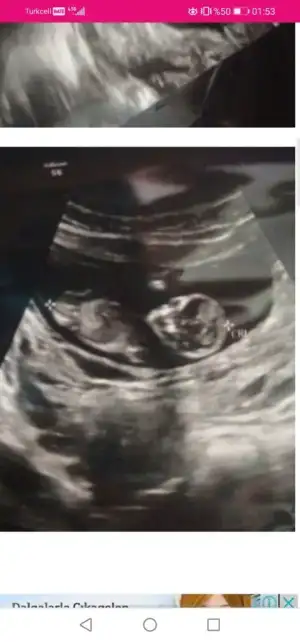

Dr erkek diye tahmin etti ama elli kere de uyardıErkek görünüyor![]()

Sanki kız gibi geldi en iyi 11 12 13 haftalar14 haftalık doktor cinsiyeti soylemediEki Görüntüle 2871448